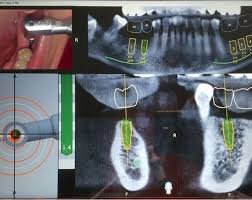

Participants were introduced to the principles of real-time 3D drill tracking, system calibration, workflow integration, and intraoperative flexibility using the NAVIDENT Navigation System.

A key component of the workshop was the live navigation-assisted surgical workflow demonstration. Attendees observed:

• Digital treatment planning protocols

• System calibration and accuracy validation

• Real-time 3D drill tracking

• Intraoperative adjustments compared to static guides